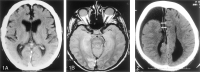

Results: Overall, the agreement rate was 91%; the insignificant disagreement rate, 7%; and the significant disagreement rate, 2%. The level of training had a significant (P =.032) effect on the rate of agreement; upper-level residents had higher rates of agreement than those of more junior residents. There were 62 false-negative findings. The most commonly missed findings were fractures (n = 18) and chronic ischemic foci (n = 12). The most common false-positive interpretations involved 10 suspected intracranial hemorrhages and suspected fractures.

Conclusion: The level of resident training has a significant effect on the rate of disagreement between the preliminary interpretations of emergency cranial CT scans by residents and the final interpretations by neuroradiologists. Efforts to reduce residents' errors should focus on the identification of fractures and signs of chronic ischemic change.